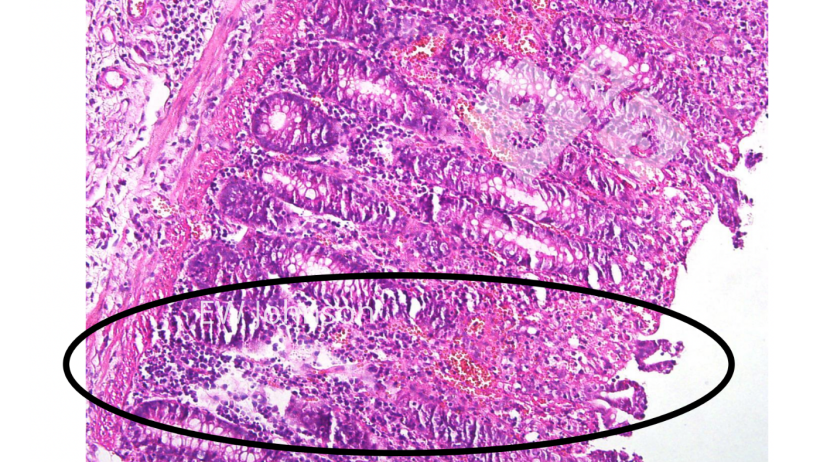

W badaniu histopatologicznym stwierdza się uogólnione zapalenie naczyń z zawałem, krwotokiem i zakrzepicą wielu narządów, zwłaszcza płuc, śledziony, węzłów chłonnych, nerek, mózgu i jelit. Dochodzi do masowego zniszczenia węzłów chłonnych i śledziony oraz wakuolizacji makrofagów pęcherzykowych. Często występuje martwica i owrzodzenie nabłonka okrężnicy (fot. 4).

Fot. 4. Zakrzepica naczyń, zawał, owrzodzenie błony śluzowej okrężnicy